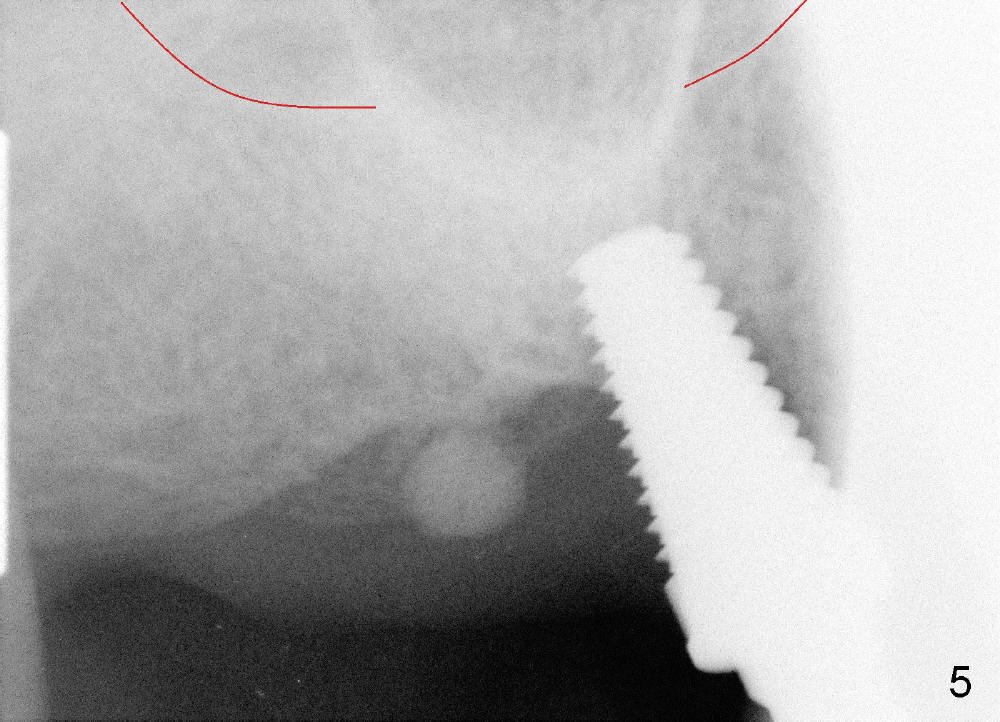

Osteotomy can be done in the palatal socket or the septum in this case to avoid implant thread exposure. Initial osteotomy is created in the palatal socket by using series of tap drills (4.5,5,6,7x17 mm) without stability or enough length (Fig.5; red line: sinus floor). The second osteotomy is made in the septum by using series of tapered osteotomes (2,3,4x17 mm), followed by 4.5x20 mm tap at depth of 17 mm with satisfactory binding (Fig.6). To avoid further sinus penetration and close the socket as much as possible, 5 and 6x17 mm taps are used at 14 mm deep (Fig.7). Nasal blowing reveals air leaking after the last tap. A 6x14 mm tapered implant is placed with insertion torque >60 Ncm (Fig.8). No bone graft is placed. The implant is surrounded by gingiva proximally and lingually and coagulation buccally. The wound is covered by perio dressing.